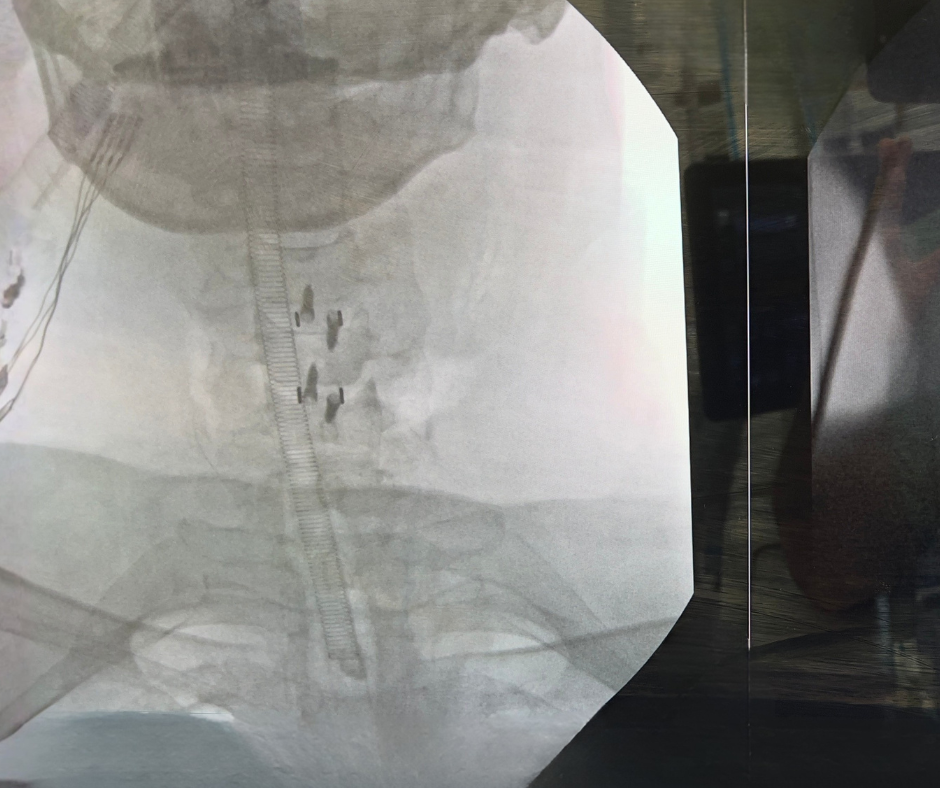

• Artrodese cervical: indicada quando é preciso estabilizar a coluna ou restaurar o espaço entre as vértebras, oferecendo melhor suporte estrutural.

Imagem de pós-operatório de artrodese para descompressão medular em paciente com mielopatia cervical